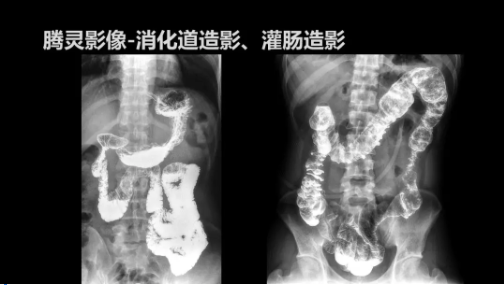

“騰靈”是安健科技的第四代動態(tài)DR產(chǎn)品,可實現(xiàn)全科室應(yīng)用。如各類常規(guī)的X線檢查、消化道檢查、骨科檢查、婦科、兒科檢查等。此外,安健科技為“騰靈”在真正意義上實現(xiàn)多科室、多功能診斷進行了多項針對性設(shè)計。

此外,“騰靈”為了能夠幫助醫(yī)生更快速、有效的定位病灶,還增加了多項精準(zhǔn)診斷保障功能,如支持動態(tài)觀察診斷,實時高清點片等?!膀v靈”透視切換高清點片曝光,捕捉關(guān)鍵病灶診斷僅需0.8s,同時還支持圖像局部放大,醫(yī)生可自由切換15’12’和9’三種放大模式,另外,“騰靈”還支持視頻保存、回放功能,幫助醫(yī)生在檢查結(jié)束后通過回放查看細(xì)節(jié),為醫(yī)生的診斷增加信心。